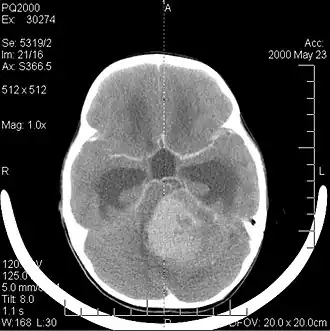

Компьютерная томография головы больного с медуллобластомой | |

Компьютерная томография

В типичных случаях на КТ медуллобластомы определяются как объёмные образования круглой или овальной формы, которые неоднородно накапливают контрастное вещество и располагаются в проекции червя мозжечка. Данные новообразования смещают IV желудочек вентрально. Достаточно часто определяются кисты (до 65 %) и микрокальцинаты[20].